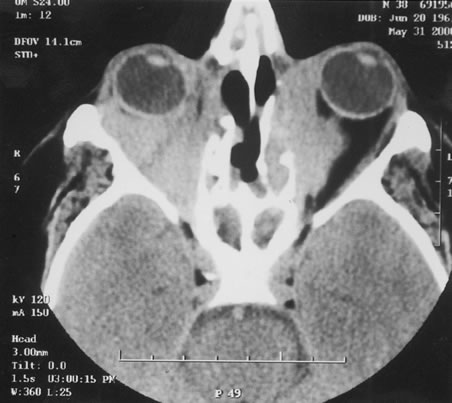

The finding of retinal vascular changes in patients with SLE correlates with the activity of the disease.214 The relationship of cotton-wool spots alone to CNS lupus has been debated, but to date no relationship has been established. Most experts feel that the finding of cotton-wool spots does not indicate the presence of CNS lupus. A much less frequent, severe retinal vasoocclusive disease has been described and does appear to be associated with CNS lupus, in particular, diffuse CNS dysfunction, such as an organic brain syndrome.214–223 This more severe retinal vasoocclusive disease may present as a central retinal artery occlusion, central retinal vein occlusion, branch artery occlusion, or most frequently, a diffuse retinal vasoocclusive process (Fig. 5), sometimes called retinal vasculitis. Although this last process sometimes has been called retinal vasculitis, the exact pathogenesis may not be true vasculitis. Cases of severe retinal vasoocclusive disease in SLE in association with the lupus anticoagulant also have been reported, and the retinal disease in these cases is presumed to be secondary to this autoantibody (Fig. 6).190,191 The prognosis for vision with this diffuse retinal vascular disease is poor and retinal neovascularization commonly develops. Panretinal photocoagulation may be of value in the treatment of the neovascularization of severe lupus retinopathy. Approximately 50% of eyes affected with this severe vaso-occlusive disease become blind. Although visual loss is common in those patients with severe retinal disease, in the more common mild retinopathy visual loss is unusual.223 Even less common than retinopathy is lupus choroidopathy, of which only a few cases have been reported to date.214,224–226 Early autopsy studies demonstrated the frequent presence of mononuclear inflammatory cells in the choroid of patients with untreated SLE.208 The clinical changes seen in patients with lupus choroidopathy include serous elevation of the retina, most often of the neurosensory retina, serous elevations of the retinal pigment epithelium, and combined elevations of both (Fig. 7). These clinical findings are associated with systemic vascular disease, either hypertension because of lupus nephritis or systemic vasculitis.226 Treatment of the underlying disease, with systemic corticosteroids and immunosuppressive agents if needed, and control of any hypertension can resolve these serous retinal detachments. Neuroophthalmic involvement in SLE includes cranial nerve palsies, lupus optic neuropathy, and central retrochiasmal disorders of vision.227–237 The central disorders include hallucinations and visual field loss.232,237 The optic nerve lesion most often seen in SLE is reported as retrobulbar optic neuritis. However, other optic nerve lesions can be seen, including anterior optic neuritis with optic disc edema, ischemic optic neuropathy, and a slowly progressive visual loss from lupus optic neuropathy.227–236 Autopsy studies have suggested that a microangiopathic process may be the pathogenesis of lupus optic neuropathy. Focal demyelination can be seen, but more severe lesions with axonal damage and even optic nerve infarcts have been demonstrated.227–229,231 One case demonstrated both demyelination and loss of axons with foci of total destruction of the optic nerve.229 This finding suggests that the same process may cause milder, reversible lesions and more severe irreversible infarct-like lesions. Transverse myelitis is seen in over 50% of patients with lupus optic neuropathy as compared with its overall frequency of 4% in patients with SLE.236 The frequency of clinical optic neuropathy in SLE patients has been estimated at 1% to 2% of patients with SLE.182–184 Scleritis occurs less commonly in patients with SLE. In one retrospective study of 97 patients with scleritis, 4% had SLE.56 Any type of scleritis may be seen, but anterior scleritis appears most commonly. Therapy that controls the underlying SLE typically controls the scleritis.2,56 |